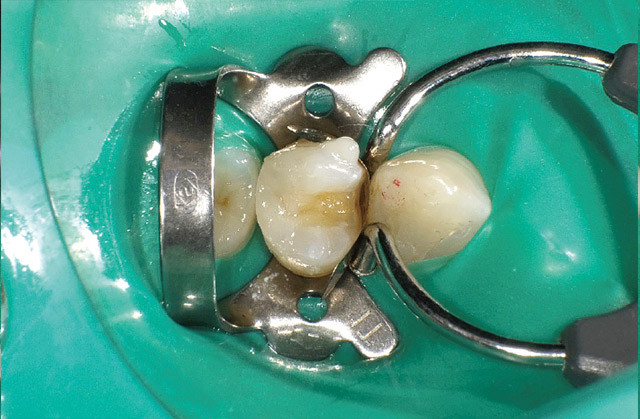

ケース2-2 コンポジタイト3Dリテーナー(フュージョンS)の設置。

-

ケース2-3 近心隣接面部の緊密な接触点の回復を目指す。